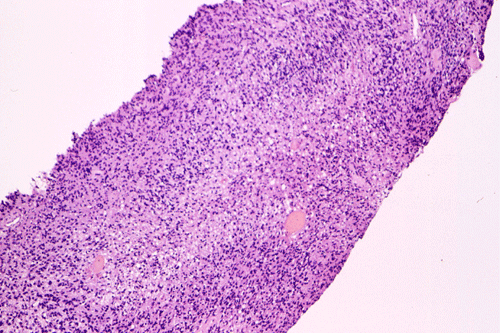

The following photos are taken from representative areas. Panel A and B are taken from intro-operative cytologic preparation. Panel C to F are taken from the frozen section. Panel G to I are taken from formalin fixed paraffin embedded material that has not been frozen. Panel J is fluorescent in situ hybridization (FISH) studies on epidermal growth factor receptor (EGFR).

A. B. C. D. E. F.

G. H. I. J.

Permenant section: The pathologic changes of the permenant sections are similar to that of frozen. Again, pseudopalisading necrosis is present (Panel G and H). Many of the nuclei are elongated and there is also considerable degree of pleomorphism.  Some of the cells have perinuclear clearing (Panel I). Positive staining for glial fibrillary acidic protein (GFAP) but not synaptophysin is demonstrated by immunohistochemistry. Although the perinuclear halo may suggestive anaplastic oligodendroglioma, the overall pathologic features, particularly the elongated nuclei and degree of pleomorphism, are that of a glioblastoma.